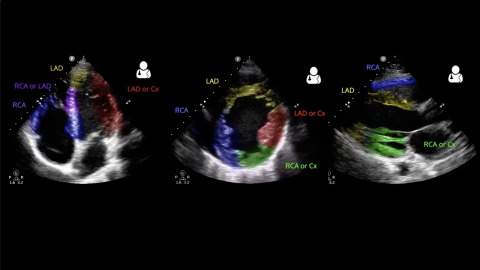

Ultrasound of Regional Wall Motion Abnormalities

Jacob Avila explains the echocardiographic findings of regional wall motion abnormalities.